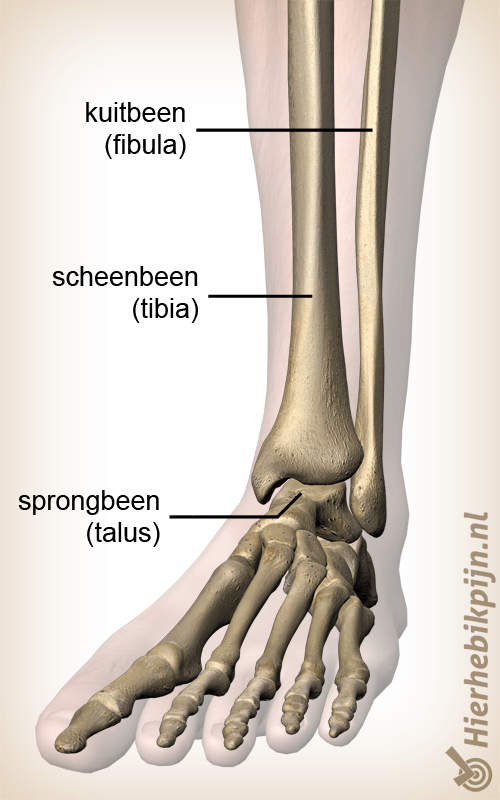

Enkel

- Fracture de la cheville

- Impingement antérieur de la cheville

- Impingement postérieur de la cheville

- Instabilité de la cheville

- Lésion du ligament interne de la cheville

- Lésion du ligament latéral externe de la cheville

- Ostéochondrite disséquante

- Syndrome du sinus du tarse

- Syndrome du tunnel tarsien